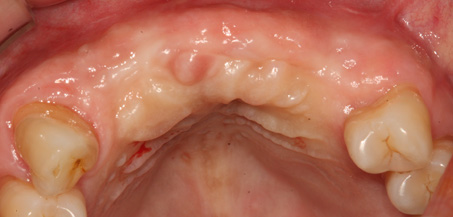

치주염 등으로 치조골(잇몸뼈)의 양이 부족한 경우

치조골 이식술을 통하여 충분한 뼈의 양을 확보한 후

임플란트를 식립합니다.

뼈의 밀도가 치밀하고 단단하며, 양이 충분할수록 임플란트의 성공률이 높아집니다.

청담네오플란트는 풍부한 경험의 의료진이 치조골 이식술을 통해 치조골을 적절한 양과

밀도로 재생시킨 후 임플란트를 식립합니다. 뼈의 흡수가 심하지 않아 적은 양의

치조골 이식을 하는 경우 임플란트 식립을 동시에 진행할 수 있지만, 뼈의 흡수가

심하여 많은 양의 치조골 이식이 필요한 경우 치조골 이식술을 먼저 진행한 후,

치조골이 재생되면 임플란트를 식립하여 보다 정밀하고 안전한 시술 결과를 얻을 수 있습니다.

치조골 이식술 전후사진